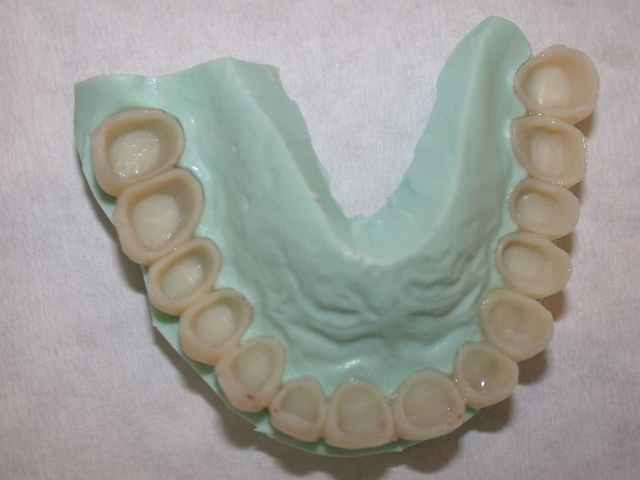

photos du travail provisoire

pour poursuivre la fin du cas la pose en mai 2006

du travail conventionnel (que j'espère définitif...)

plusieurs remarques :

je me suis un peu battu avec cette patiente pour la maintenance (bloc incisif inférieur..)

teinte A1 souhaitée par la patiente.

j'ai d'ailleurs réalisé un blanchiment en 2007 des 4 incisives inférieures pour aligner la teinte (en fait une fois que la maintenance a été meilleure ).